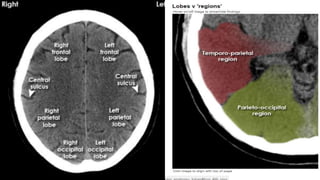

LOBES

TEMPORAL LOBE CONTOURING Francis Ho, MEDICEINE,2018